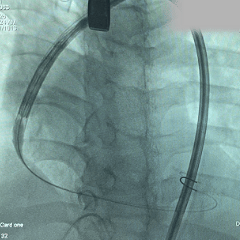

术中影像

根部造影:可见大量反流

导丝跨瓣

预弯型系统顺利跨过横位心

平齐窦底猪尾,0位定位

展开后造影,瓣膜位置偏深